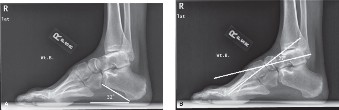

The correct answer is (A). Radiographic characteristics of a pes cavus deformity include an elevated dorsiflexion pitch of the calcaneus, so that the angle between the calcaneus and the floor often exceeds 30 degrees on weight-bearing radiographs (Fig. 5–5A). A plantar-flexed first ray may also be characteristic, in which case the straight line normally formed by the talus and the first metatarsal on lateral radiograph is abnormal. This is known as Meary’s angle (Fig. 5–5B).

--- _Figure 5–5_A: Elevated dorsiflexion pitch of the calcaneus with pes cavus. B: Abnormal Meary’s angle with pes cavus. Pes planus is further characterized by hindfoot varus and forefoot valgus. Adult-acquired flatfoot deformity would be characterized by hindfoot valgus and forefoot varus.